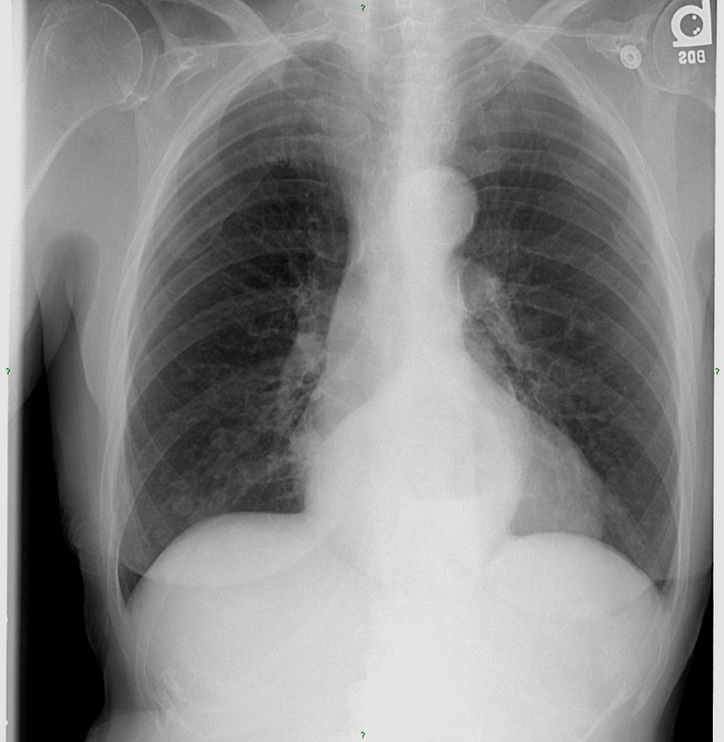

1. Describe the main finding.

2. Do you have a diagnosis or a differential diagnosis?

3. What additional view would you like to see to help narrow your differential list or to make the diagnosis?